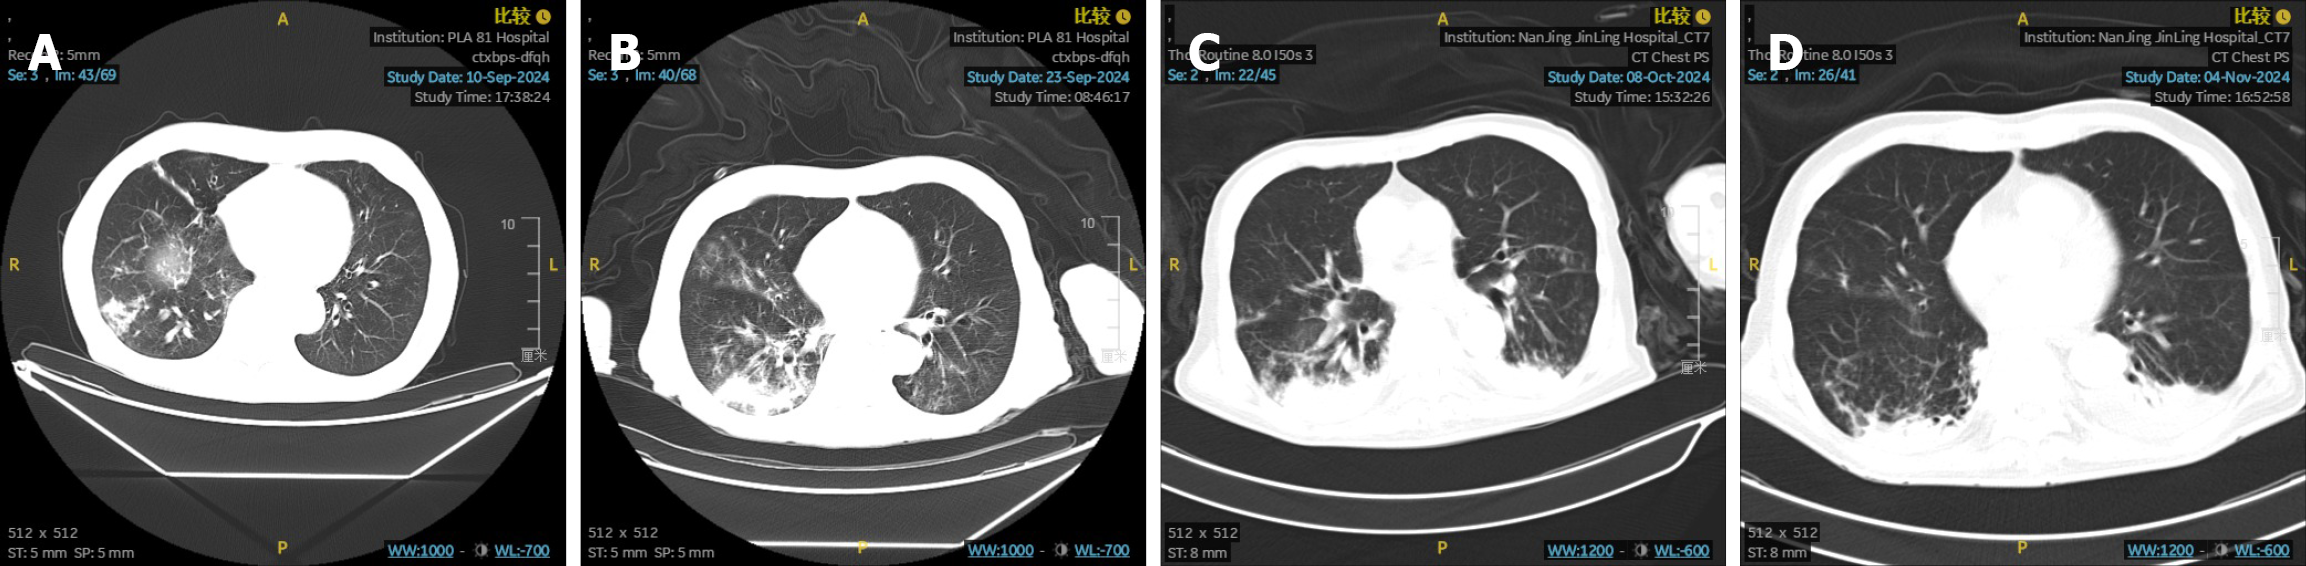

On September 10, 2024, the patient was diagnosed with pneumonia and treated with cefoperazone sulbactam sodium combined with moxifloxacin in the Emergency Department. Subsequently, on September 23, 2024, the patient was admitted to the Respiratory Department and treated with piperacillin and tazobactam due to the worsening infection. On October 8, 2024, the patient required admission to the intensive care unit and was administered imipenem and cilastatin due to further aggravation of the infection. A chest CT scan conducted on November 4, 2024, revealed bronchiectasis with infection in the right lung. Subsequently, there was clinical and radiological improvement (Figure 3). During the anti-infective treatment, the use of sintilimab and S-1 was discontinued. Following discharge from the hospital, due to the patient’s poor physical condition, the patient requested a temporary discontinuation of antitumor treatment. After thorough communication, the patient opted for close observation and follow-up. From September 2024 to February 2025, the patient did not undergo any antitumor therapy. A CT scan on March 7, 2025, indicated that the liver lesions continued to shrink, with target lesions reduced by 79.4% (Figure 2). Subsequently, on March 12, April 9, and May 19, 2025, the patient received three cycles of maintenance therapy with sintilimab combined with S-1 (sintilimab 200 mg IV on day 1; S-1 40 mg in the morning and 60 mg in the evening from day 1 to day 14, every 3 weeks). The patient tolerated the therapy well, with the main adverse reactions being grade 1 anemia and grade 1 fatigue, which were considered primarily related to chemotherapy and not associated with sintilimab.